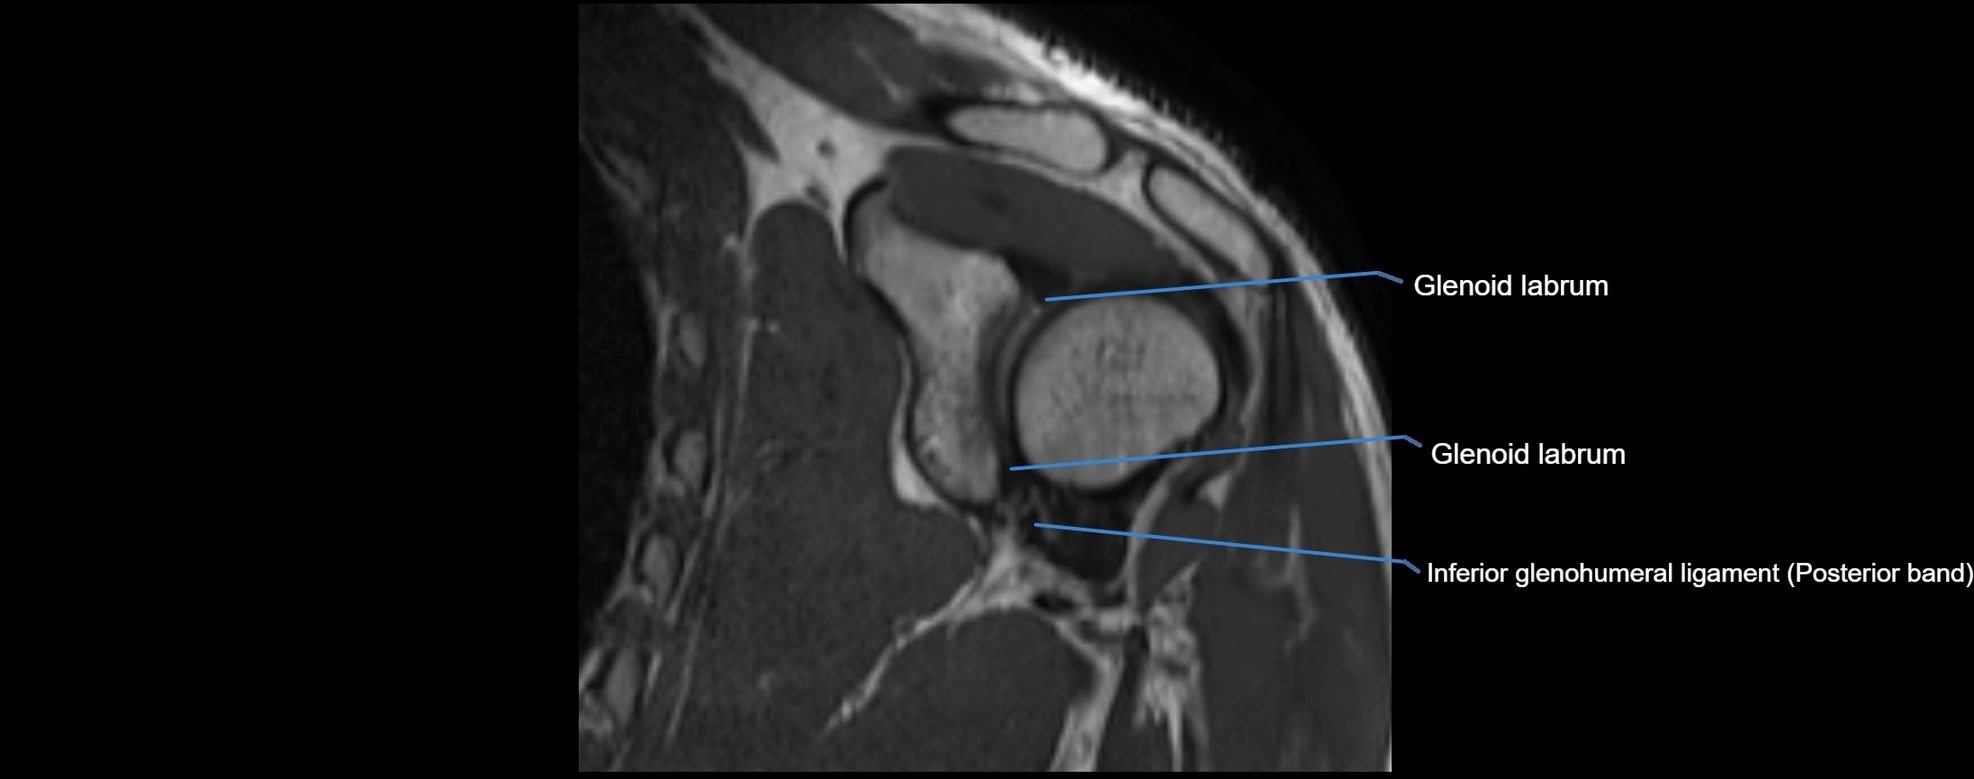

CT image

image